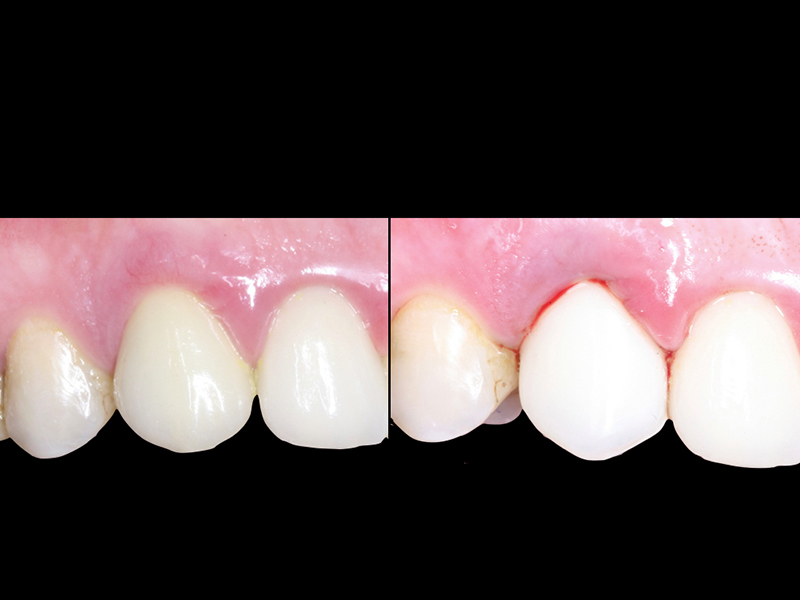

- Fixação da Prótese: Em até 72 horas após a cirurgia, a prótese provisória é instalada, permitindo que o paciente recupere a funcionalidade e a estética imediatamente.

- Recuperação rápida: O paciente sai do consultório com um sorriso renovado em questão de dias.

- Conforto e Estética: A prótese provisória é funcional e visualmente semelhante aos dentes naturais.